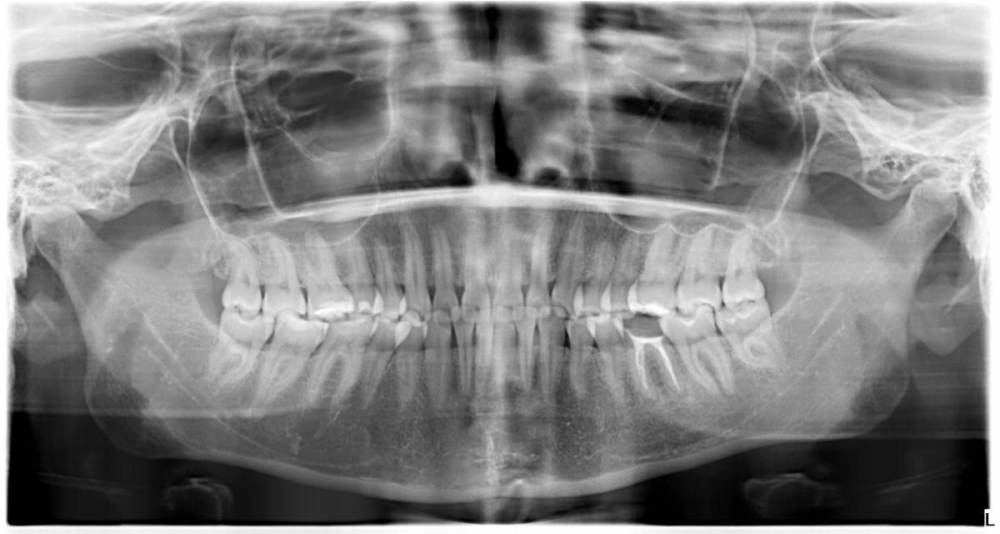

Котенька Опубликовано 2 декабря, 2022 Автор Поделиться Опубликовано 2 декабря, 2022 3 часа назад, karasov сказал: Если их хорошо чистить-показания к удалению стремятся к нулю. Лично я считаю ,что восьмерки маловероятно что-то сдвигают во фронтальном отделе нижней челюсти. Если по каким-либо причинам изначально челюсть мала, а зубов много и они крупные-будет и скученность во фронтальном отделе и ретенция/дистопия третьих моляров Небольшая скученность всё же есть и неправильное положение некоторых зубов на нижней челюсти.Одна из нижних мудростей немного дистопирована,выросла немного к щеке,но не мешает. А есть ли на снимке признаки того,что восьмёрки сдвинули зубы и внизу и вверху? Мне кажется есть у остальных моляров наклон из-за выросших зубов мудрости. Ссылка на комментарий

Irouil Опубликовано 3 декабря, 2022 Поделиться Опубликовано 3 декабря, 2022 18 часов назад, Котенька сказал: А почему может быть такая вероятность,в чем возможная причина,на ваш взгляд? Чаще всего при подобной рентген картине как у Вас вокруг нижних зубов мудрости отсутствует специально обученная слизистая, которую мы называем «прикрепленной», без которых вокруг зубов высока вероятность формирования пародонтальных карманов, рецессий, кариесов корня и инфекционных осложнений с распространением в окружающие ткани. В соответствующем этим зубам местоположении это чревато операциями, проводимыми через кожу по шее, что, безусловно, является крайне неприятным вариантом развития событий из-за сохранения нефункциональных, по большому счёту, зубов Ссылка на комментарий

Irouil Опубликовано 5 декабря, 2022 Поделиться Опубликовано 5 декабря, 2022 2 часа назад, karasov сказал: Почему вы считаете,что третьи моляры у данного пациента не функциональны? Я написал, что «по большому счёту нефункциональны». А что - третьи моляры активно участвуют в жевании? Это, вроде как, не секрет, что бОльшая часть эффективного жевания ограничивается вообще первыми молярами (собственно, протезирование зубных рядов по первые моляры на сегодняшний день - скорее правило, чем исключение), а попадание пищевого комка на корень языка, в пограничную с ротоглоткой область (где, собственно, и находятся нижние третьи моляры), скорее происходит в связи с его глотанием, а не жеванием. 3 часа назад, karasov сказал: Судить о качестве слизистой по панораме невозможно. Косвенно - возможно: дистальный край нижнего моляра упирается в передний край восходящей ветви нижней челюсти, а там слизистая исключительно подвижная. Афанасьев определял минимальное рентгенологическое ретромолярное расстояние (как раз между двумя описанными структурами) в 5 мм, тут примерно нисколько мм. Единственный вариант наличия тут прикрепленки вокруг нижних 8-ок - это их сильный язычный завал 3 часа назад, karasov сказал: Вероятность осложнений с ,,операциями,проводимыми через кожу на шее,, также невозможно оценить. Подобные операции могут произойти и от проблем с любыми иными зубами. Могут то могут, человеку и на голову кирпич упасть может, если же исходить из вероятностной частоты осложнений, то тут я с Вами в корне не согласен - ретромолярный абсцесс, в некоторых случаях за считанные дни и даже часы распространяющийся в крылочелюстное пространство является практически аналогом пародонтального, который никакой угрозы здоровью пациента в области любого другого зуба не несёт. А перикорониты - это вообще гингивит, возникает элементарно, в хронической форме присутствует почти всегда, а в обострении также легко дисеминирует под челюсть. Пару месяцев дежурств в гнойной члх смывают виртуальную тождественность между степенью угроз транскутанных доступов для дренажей одонтогенных гнойников от третьих нижних моляров и «любых иных зубов» 3 часа назад, karasov сказал: Также можно долго рассуждать о их применении при возможной аутотрансплантации при необходимости, вместо других зубов. Многовато условий должно сойтись, первое из которых - удаление восьмерки без фрагментации. Даже в конкретном кейсе вероятность подобного расклада далека от 100%, показания у метода только для замещения других моляров. При наличии показаний к удалению восьмерок, такой сомнительный профит я бы в расчёт не брал. 3 часа назад, karasov сказал: Это как с аппендиксом-есть у большинства,но воспаляется далеко не у всех. Я не указывал, что ТС безусловно показано удаление восьмерок, с самого начала сказал, что нужен очный осмотр, но в абсолютном большинстве случаев у пациентов с подобной рентген картиной показания к удалению присутствуют. 3 часа назад, karasov сказал: Более того сам являюсь обладателем полноценнофункционирующих восьмерок, которые тщательно чищу. Для чего их мне удалять? Открывайте собственную тему, выкладывайте снимки - обсудим!) 1 Ссылка на комментарий